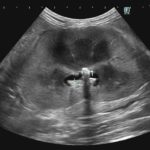

急性腎機能障害の猫ちゃんが(BUN>130mg/dl、Cre>14mg/dl、高カリウム血症)治療のため救急で対応しました。無麻酔CTでは両側に尿管結石が確認されました。著しく拡張している左腎の腎盂に一時的な腎瘻カテーテルを設置し、尿の排泄路の確保を行います。しかし、腎数値に改善は見られませんでした。腎盂造影を行うと拡張している腎臓において尿の産生と排泄は行われている様です。一方、腎盂拡張のほとんどない右腎の腎盂造影では尿の排泄が確認されません。今回の急性腎機能障害の原因は機能の残っていた右腎の急性尿管閉塞による急性腎障害と診断しました。左腎に関しては尿の産生はあるものの慢性腎機能障害であり、すでに尿濃縮能は失われていると判断しました。右腎の問題に対して尿管膀新吻合短尺型ステント設置術を行いました。術後は徐々に腎数値は低下し、腎機能の回復が得られました。一見すると腎盂拡張の顕著な側が急性腎障害の責任病変と判断しがちですが、片腎が十分に機能していれば腎数値に影響はほとんどなく、どちらの腎臓を治療対象とするか?エコー、CTなどの画像診断、血液検査、一時的な腎瘻カテーテルの設置、腎盂造影など総合的な判断が必要です。また判断がつかず、左右同時に治療が必要な場合もあります。